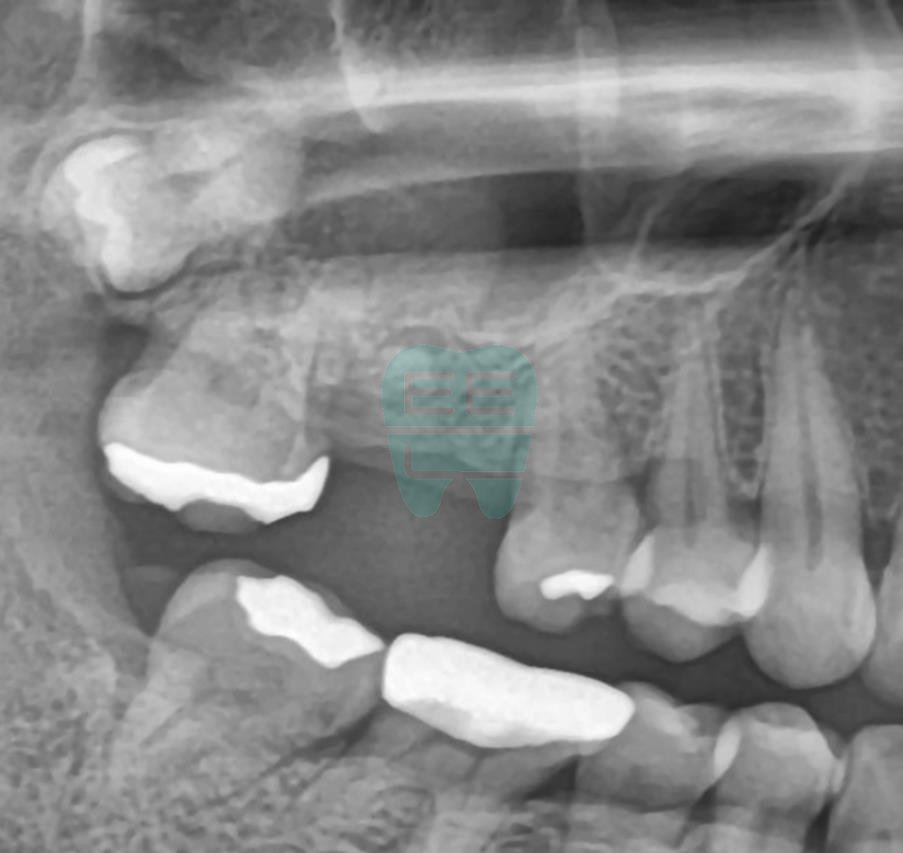

**Pre-operative Panoramic X-ray** — Confirming proximity to the maxillary sinus.

**Post-operative Panoramic X-ray** — Implant securely positioned.